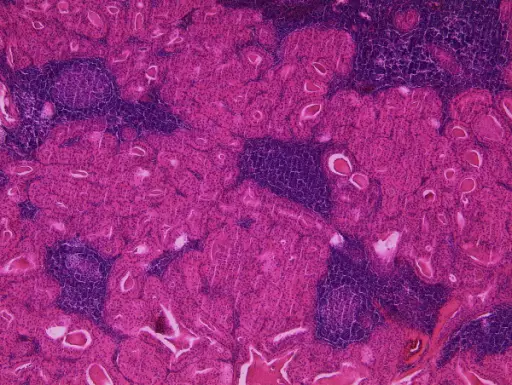

Warthin tumor is a benign cystic tumor with a stroma that resembles a lymph node and many lymphocytes.

Warthin tumor is also known as papillary cystadenoma lymphomatosum.

Warthin tumor is the second most common salivary gland tumor.

Warthin tumor occurs almost invariably in the parotid.